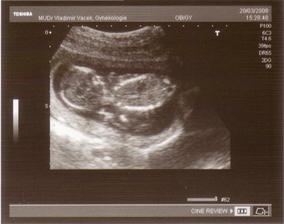

20.3. máme za sebou UTZ screening,tatka byl s náma.Vše dopadlo na výbornou čekáme zdravý miminko